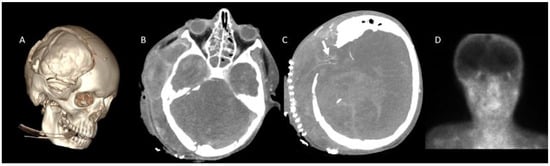

2.1. Study Population

- Nunes, D.M.; Maia, A.C.M., Jr.; Boni, R.C.; da Rocha, A.J. Impact of skull defects on the role of CTA for brain death confirmation. AJNR Am. J. Neuroradiol. 2019, 40, 1177–1183. [Google Scholar] [CrossRef] [PubMed]

- Almus, E.; Bıyıklı, E.; Yapıcı, Ö.; Almus, F.; Girgin, F.İ.; Öztürk, N. Brain death in children: Is computed tomography angiography reliable as an ancillary test? Pediatr. Radiol. 2023, 53, 131–141. [Google Scholar] [CrossRef]